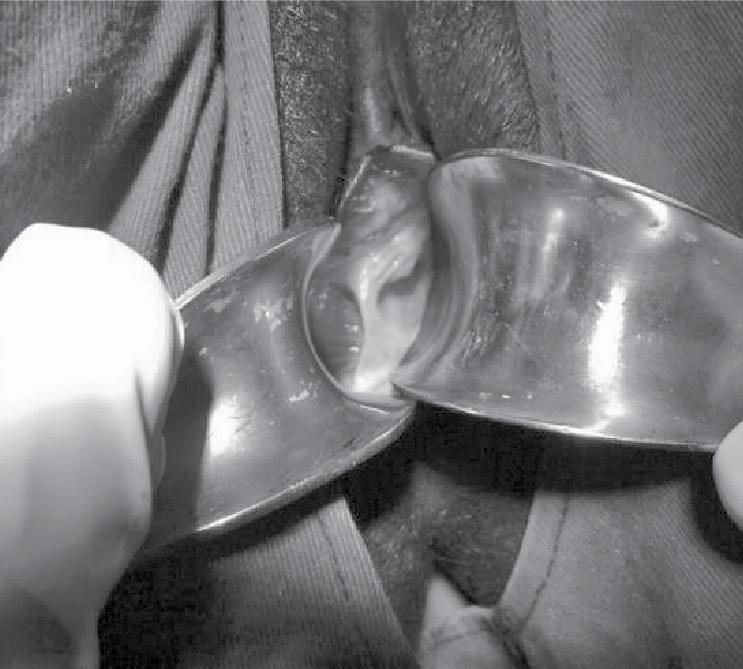

speculum examination revealed complete vertical vaginal septum (Fig. 1) and

bulging of vaginal fornices in right hemivagina, active clear liquor leak

demonstrated on the blade of speculum in right hemivagina. Internal examination

revealed right cervix was partially effaced and 2 cm dilated and presenting

part at minus three station, and in left hemivagina cervix was uneffaced and os

closed.

Figure 1. Per speculum examination showing right and left hemivagina with complete vertical vaginal septum.